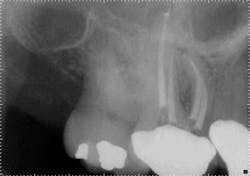

When the anatomy is more complicated than can be predictably treated with WaveOne, but not so irregular as to require all of the files of Vortex Blue, is there another option? It is in these clinical situations that ProTaper Next® (Dentsply Tulsa Dental Specialties) becomes the best file system (Figs. 5 and 6). The rectangular but off-center cross-section creates the illusion that the canal is slightly larger than it is because the alternating contact points of the file prevent the feeling of the file getting locked into the canal space. This added space along the file results in additional room for debris removal, and in spite of this design, there is no appreciable loss of cutting efficiency. When using ProTaper Next files to create the final root canal shape, two or three instruments will be used.

Fig. 5: With a crown in place, it can be difficult to determine the size of the pulp chamber. However, at the level of the roots, the canals in tooth No. 3 look to have calcified compared to the neighboring teeth.

Fig. 6: After locating the canals and following the glide path to the root ends with hand files, two ProTaper Next files were used in each root canal to create the final shape.